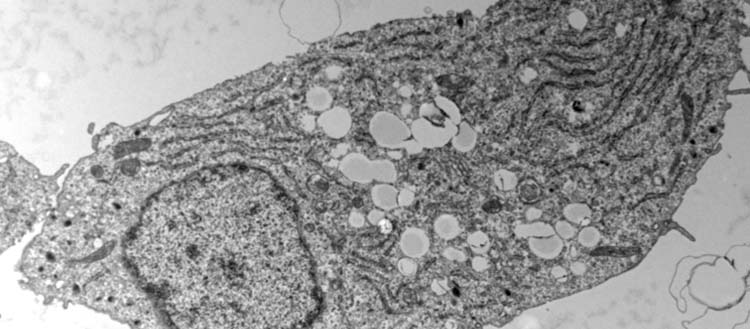

Pancreatic beta cell under electronic microscopy. The white circles visible in the centre of the cell correspond to fat storage droplets. (© UNIGE - laboratoire Maechler)

In order to differentiate the effect of fat from that of sugar, the scientists exposed beta cells to an excess of sugar, of fat, and then to a combination of the two. The toxicity of sugar was first confirmed: beta cells exposed to high sugar levels secreted much less insulin than normal. “When cells are exposed to both too much sugar and too much fat, they store the fat in the form of droplets in anticipation of less prosperous times”, explains Lucie Oberhauser, a researcher in the Department of Cell Physiology and Metabolism at the UNIGE Faculty of Medicine, and first author of this work. “Surprisingly, we have shown that this stock of fat, instead of worsening the situation, allows insulin secretion to be restored to near-normal levels. The adaptation of beta cells to certain fats would thus contribute to maintain normal blood sugar levels.”